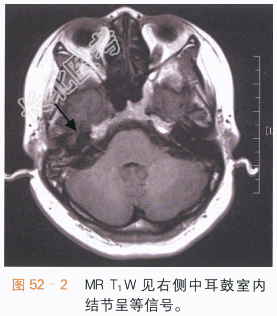

读片分析:面神经鞘瘤多见于面神经位于内耳与鼓室交界处的膝状神经节的面神经管内,它使面神经管扩大,CT扫描可见鼓室内沿后壁的软组织结节影及周围骨质的吸收或破坏,如图52-1所示,在MR图像上,面神经瘤呈等或等高信号,具轻度强化,如图52-2~图52-4所示,面神经鞘瘤主要的临床症状是面神经麻痹或面肌痉挛,可伴听力下降。由于患者临床症状出现较早,因此初次发现的面神经鞘瘤通常不大,需要我们仔细地进行影像学观察,否则容易遗漏。生长得比较大的面神经瘤,可以见到神经鞘瘤特有的囊实性结节,及其相应的影像学表现。